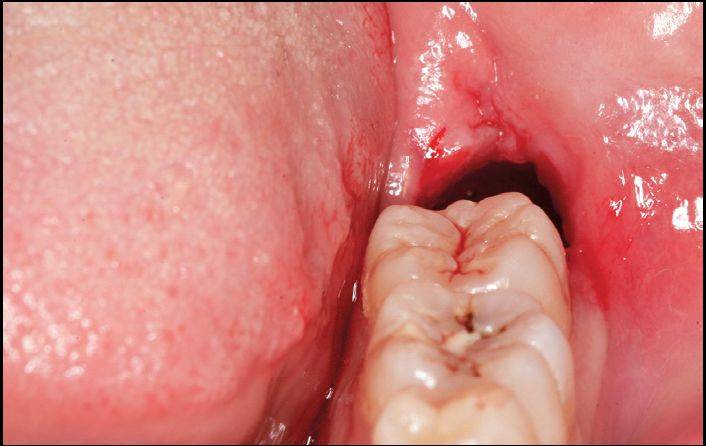

如下面的一个阻生智齿,可有三种拔除方法:

①劈开法:切开、翻瓣、去骨(凿)、劈开、挺除;

②钻拔法:切开翻瓣、去骨(钻)、分牙、挺;

③直接分牙拔除法:分牙拔除法(潜钻),可不切开、不翻瓣、不去骨拔除。

A.水平智齿仅露出远中牙冠

B.X线显示阻生智齿水平中位

C.直接分牙法并未切开、翻瓣、去骨拔除

D.智齿拔除,牙槽窝完好

同样的阻生智齿的不同拔除方法